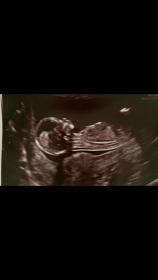

Hello this is my 13 week scan pics , was wondering if there are any experienced nub/skull theory mummy's on this site. I'd love some guesses thank you in advance xx[ATTACH=CONFIG]27776[/ATTAttachment 27777ACH]

Leaning girl

Girly lean.

A few people have said it looks girly how exciting These are the only ones I have unfortunately . I'll be finding out on the 23rd X